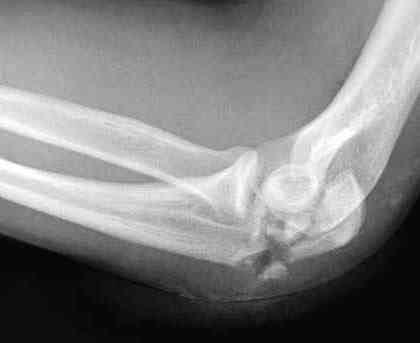

Здесь выставлены несколько случаев и варианты фиксации локтевого отростка, некоторые в комбинации с другими переломами.

перелом локтевого отростка с переломом головки лучевой кости (использованы 2 мм шурупы)

3 вариант